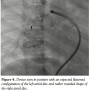

single and the narrow segment measured 14 mm with the proximal portion measuring 26 mm. Considering the morphology of the fistula, we decided to close the defect antegradely. As the fistula was large and roomy we decided to close the feeding vessel with an atrial septal occluder. The left atrial disc would easily be accommodated in the aneurysmal sac and the right atrial disc was expected to configure into the shape of the feeding artery without protruding into the lumen of RPA. The constricted segment was well away from the branches of the RPA as well as the opening of the pulmonary veins into the left atrium. The balloon was removed and an 8 Fr long Cook sheath was introduced antegradely over the Amplatz wire through RPA, across the fistula into the LA. As the constricted segment measured 14 mm, we deployed a 16 mm Cardiofix atrial septal occluder (Starway Medical Corporation) across the narrow portion of the feeding vessel. While the left atrial disc assumed the expected shape, the right atrial disc was rounded due to comparatively less space in the feeding artery. We did RPA injections in multiple views to be sure that there was no obstruction to RPA flow as well as that there is no residual flow across the fistula (Figure 3, Video 3). After checking the stability of the device, it was released (Figure 4, Video 4). The patient’s saturation improved to 100% and there was no residual fistula on follow-up. He was put on oral aspirin for 6 months and is doing well on follow-up without any complications.